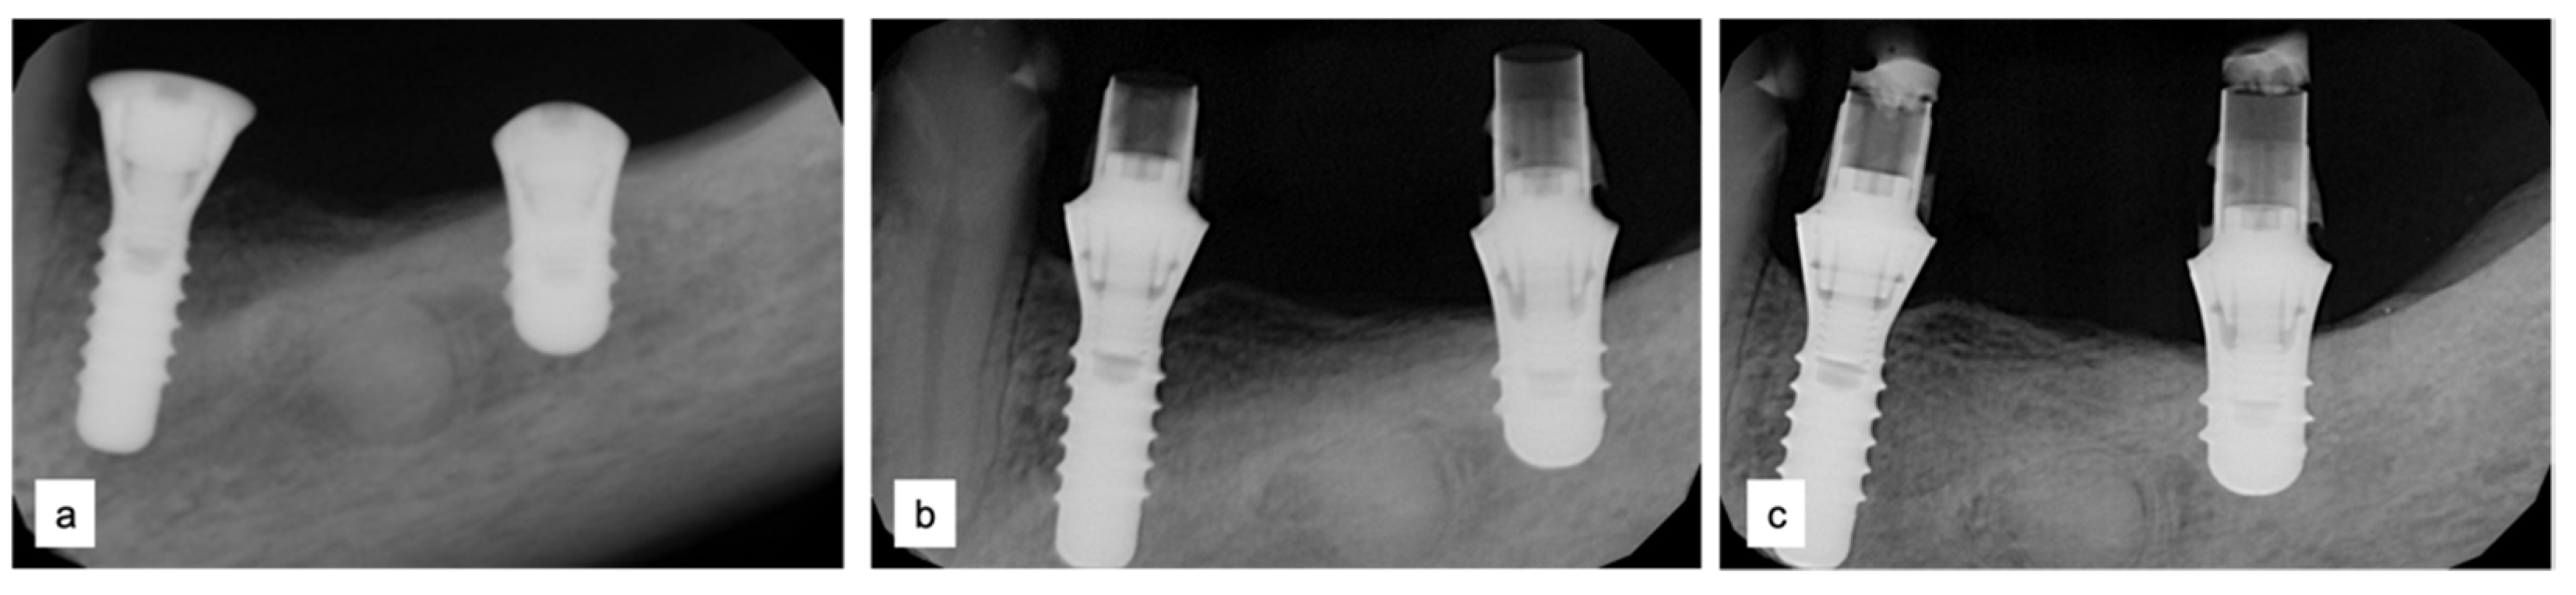

3.4. Implant Insertion

| T3 | Implant Placement (11 months) | Straumann implant (Institute Straumann, Basel, Switzerland) |